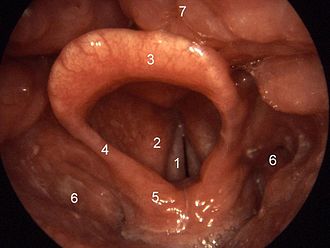

Na nastanak barotraume pluća utječe zadržavanje daha tijekom izranjanja jer se plin u plućima zadržava na povišenom tlaku u stlačenom stanju, a zatvoren grkljan sprječava da se plin sa snižavanjem tlaka tijekom izrona širi i izbacuje iz organizma, kako bi pluća postigla prvobitni volumen prije početka ronjenja.

Problem nastaje samo ako ronioca uhvati panika tijekom koje nepravilno diše i grčevito zatvara glotis i stlačeni zrak zadržava u plućima do površine vode, što izaziva njegovo širenje koje je veće od plućnih volumena.

- Prozračivanje zračnog prostora u ušima i sinusima. Da bi spriječio opasnost od pucanja bubnjića, ronilac može koristiti valsalva manevar, kako bi višak zraka u srednjem uhu preko eustahijeve tube izišao u područje ždrijela. Ponekad gutanje otvara eustahijevu cijev i izjednačava tlak u ušima.